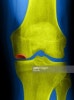

CT : 대퇴과 골괴사(Osteonecrosis of the femoral condyle)

MRI : 대퇴과 골괴사(Osteonecrosis of the femoral condyle)